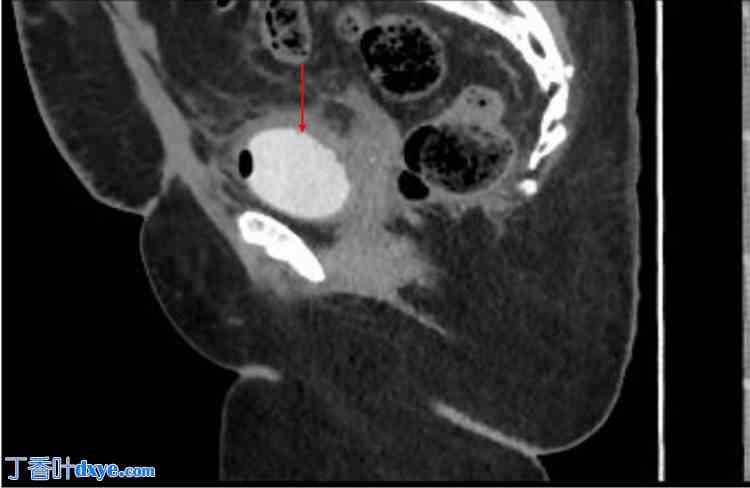

术后5个月,她再次因同样的症状来到院门诊就诊。作者进行了尿培养和CT膀胱造影检查,并给予抗生素治疗直至出院。 CT膀胱造影显示膀胱上缘与阴道之间存在一条约7×4.5 mm的瘘管(如图1箭头所示)。CT膀胱造影两天后,根据造影结果,安排患者进行诊断性膀胱镜检查和腹腔镜检查。膀胱镜检查发现右侧输尿管2-3 cm处、左侧输尿管2 cm处存在一条6×5 mm的膀胱阴道瘘(VVF)。诊断性腹腔镜检查发现大网膜主要粘连于左侧腹前壁,肠道粘连于左侧腹前壁,大网膜与乙状结肠紧密粘连,大网膜与膀胱粘连,膀胱与盆壁粘连。

图1. 术前增强CT膀胱造影。

红色箭头指向膀胱。绿色箭头指向瘘管,蓝色箭头指向阴道。